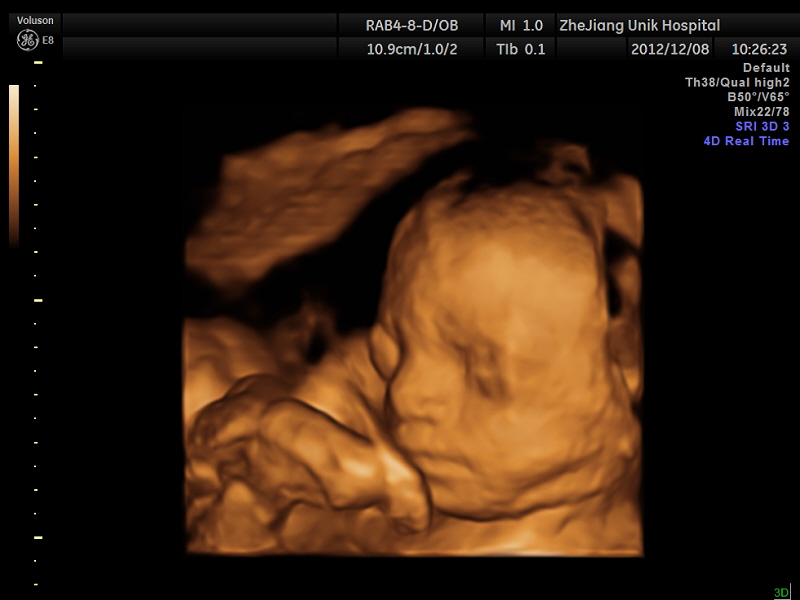

p>优你可妇科门诊部是杭城为数不多的同时拥有三维,四维彩超的医疗

新闻中心 综合 > 正文 三维彩色b超可以清楚看到胎儿的一举一动.